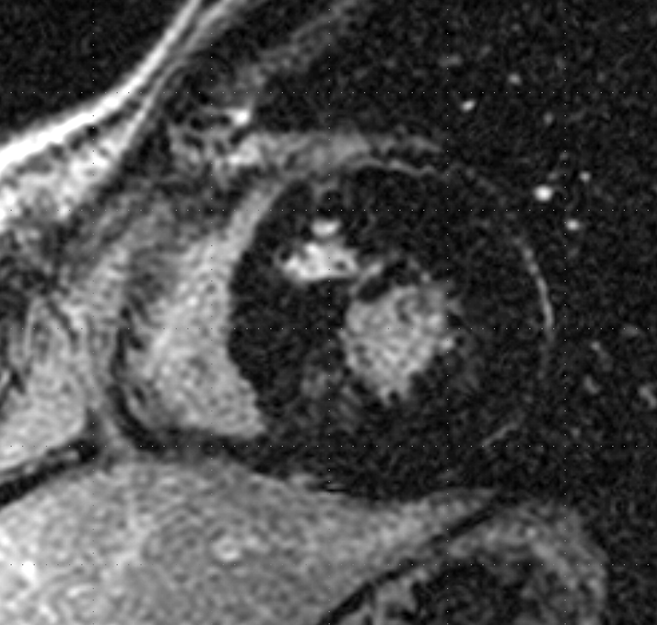

La nivelul miocardului hipetrofic sunt adeseori prezente așa numitele cripte -niște crevase ce străbat mușchiul care devine astfel foarte subțire- și care in cazul unei secționări cu bisturiul pot duce la perforarea acestuia. Identificarea criprelor se poate face doar cu ajutorul rezonanței magnetice.

Figura 4. Prezența criptelor miocardice identificate la explorarea prin rezonanță magnetică cardiacă.